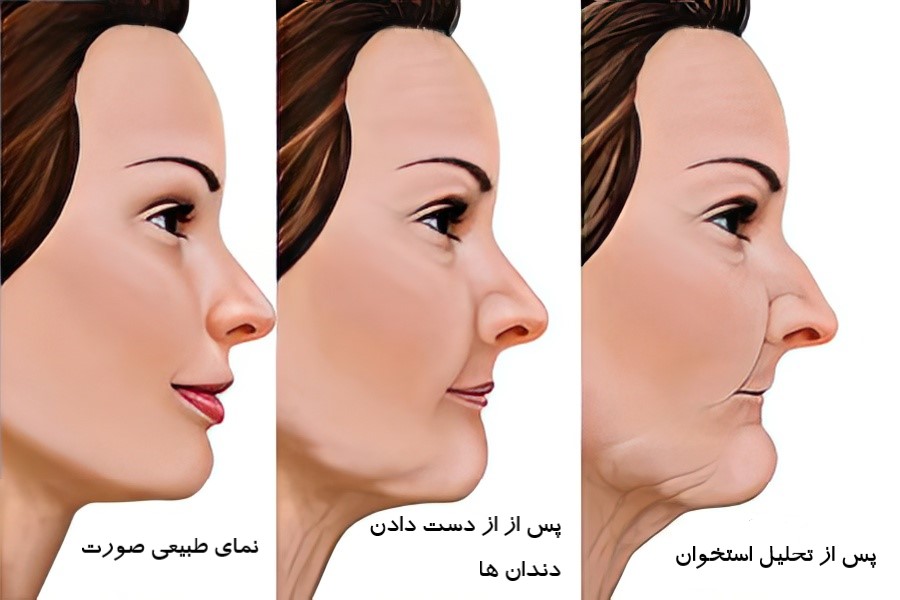

عوارض بی دندانی بر زیبایی صورت، بیدندانی فقط جویدن و صحبت کردن را سخت نمیکند؛ دندانها چهره را شکل میدهند. وقتی فرد یک یا چند دندان خود را از دست میدهد، لبها و گونهها فرو میروند و چین و چروک اطراف دهان بیشتر میشود. درمان بی دندانی میتواند این تغییرات را کاهش دهد و فرم طبیعی لبها و گونهها را بازگرداند. این تغییرات ظاهر فرد را مسنتر و خستهتر نشان میدهند و میتوانند اعتماد به نفس او را کاهش دهند. شناخت عوارض بیدندانی و جایگزینی دندان های از دست رفته اهمیت زیادی دارد.

نقش دندان ها در حفظ فرم طبیعی صورت

دندان ها لبها، گونهها و استخوان فک را حمایت میکنند و فرم طبیعی صورت را حفظ میکنند.

وقتی دندانها سالم هستند:

- ارتفاع صورت متعادل است

- لبها پر و طبیعی دیده میشوند

- گونهها شاداب و پرحجم میمانند

- چینوچروک اطراف دهان کمتر دیده میشود

وقتی دندانها از دست میروند، لبها فرو میروند، گونهها افتاده میشوند و صورت پیرتر دیده میشود. جایگزینی دندان ها فرم طبیعی صورت را حفظ میکند.

تحلیل استخوان فک پس از از دست دادن دندان

دندانها فشار جویدن را به استخوان فک منتقل میکنند و حجم استخوان را حفظ میکنند.

با از دست دادن دندانها:

- استخوان فک تحلیل میرود

- لبها و گونهها کمتر حمایت میشوند

- ظاهر صورت تغییر میکند و پیرتر دیده میشود

تحلیل استخوان همچنین درمانهایی مثل ایمپلنت را دشوار میکند. بنابراین، جایگزینی سریع دندان ها اهمیت بالایی دارد.

کاهش ارتفاع صورت و تغییر پروفایل چهره

دندانها ارتفاع صورت را حفظ میکنند.

با از دست دادن دندانها:

- فاصله بین بینی و چانه کاهش مییابد

- صورت کوتاه و فشرده دیده میشود

- پروفایل صورت تغییر میکند

جایگزینی سریع دندان ها ارتفاع صورت و پروفایل را متعادل نگه میدارد.

پیرتر دیده شدن افراد بی دندان

بی دندانی ظاهر فرد را پیرتر نشان میدهد.

دلایل:

- تحلیل استخوان فک

- کاهش ارتفاع صورت

- فرو رفتگی لبها و گونهها

- چینوچروک عمیق اطراف دهان